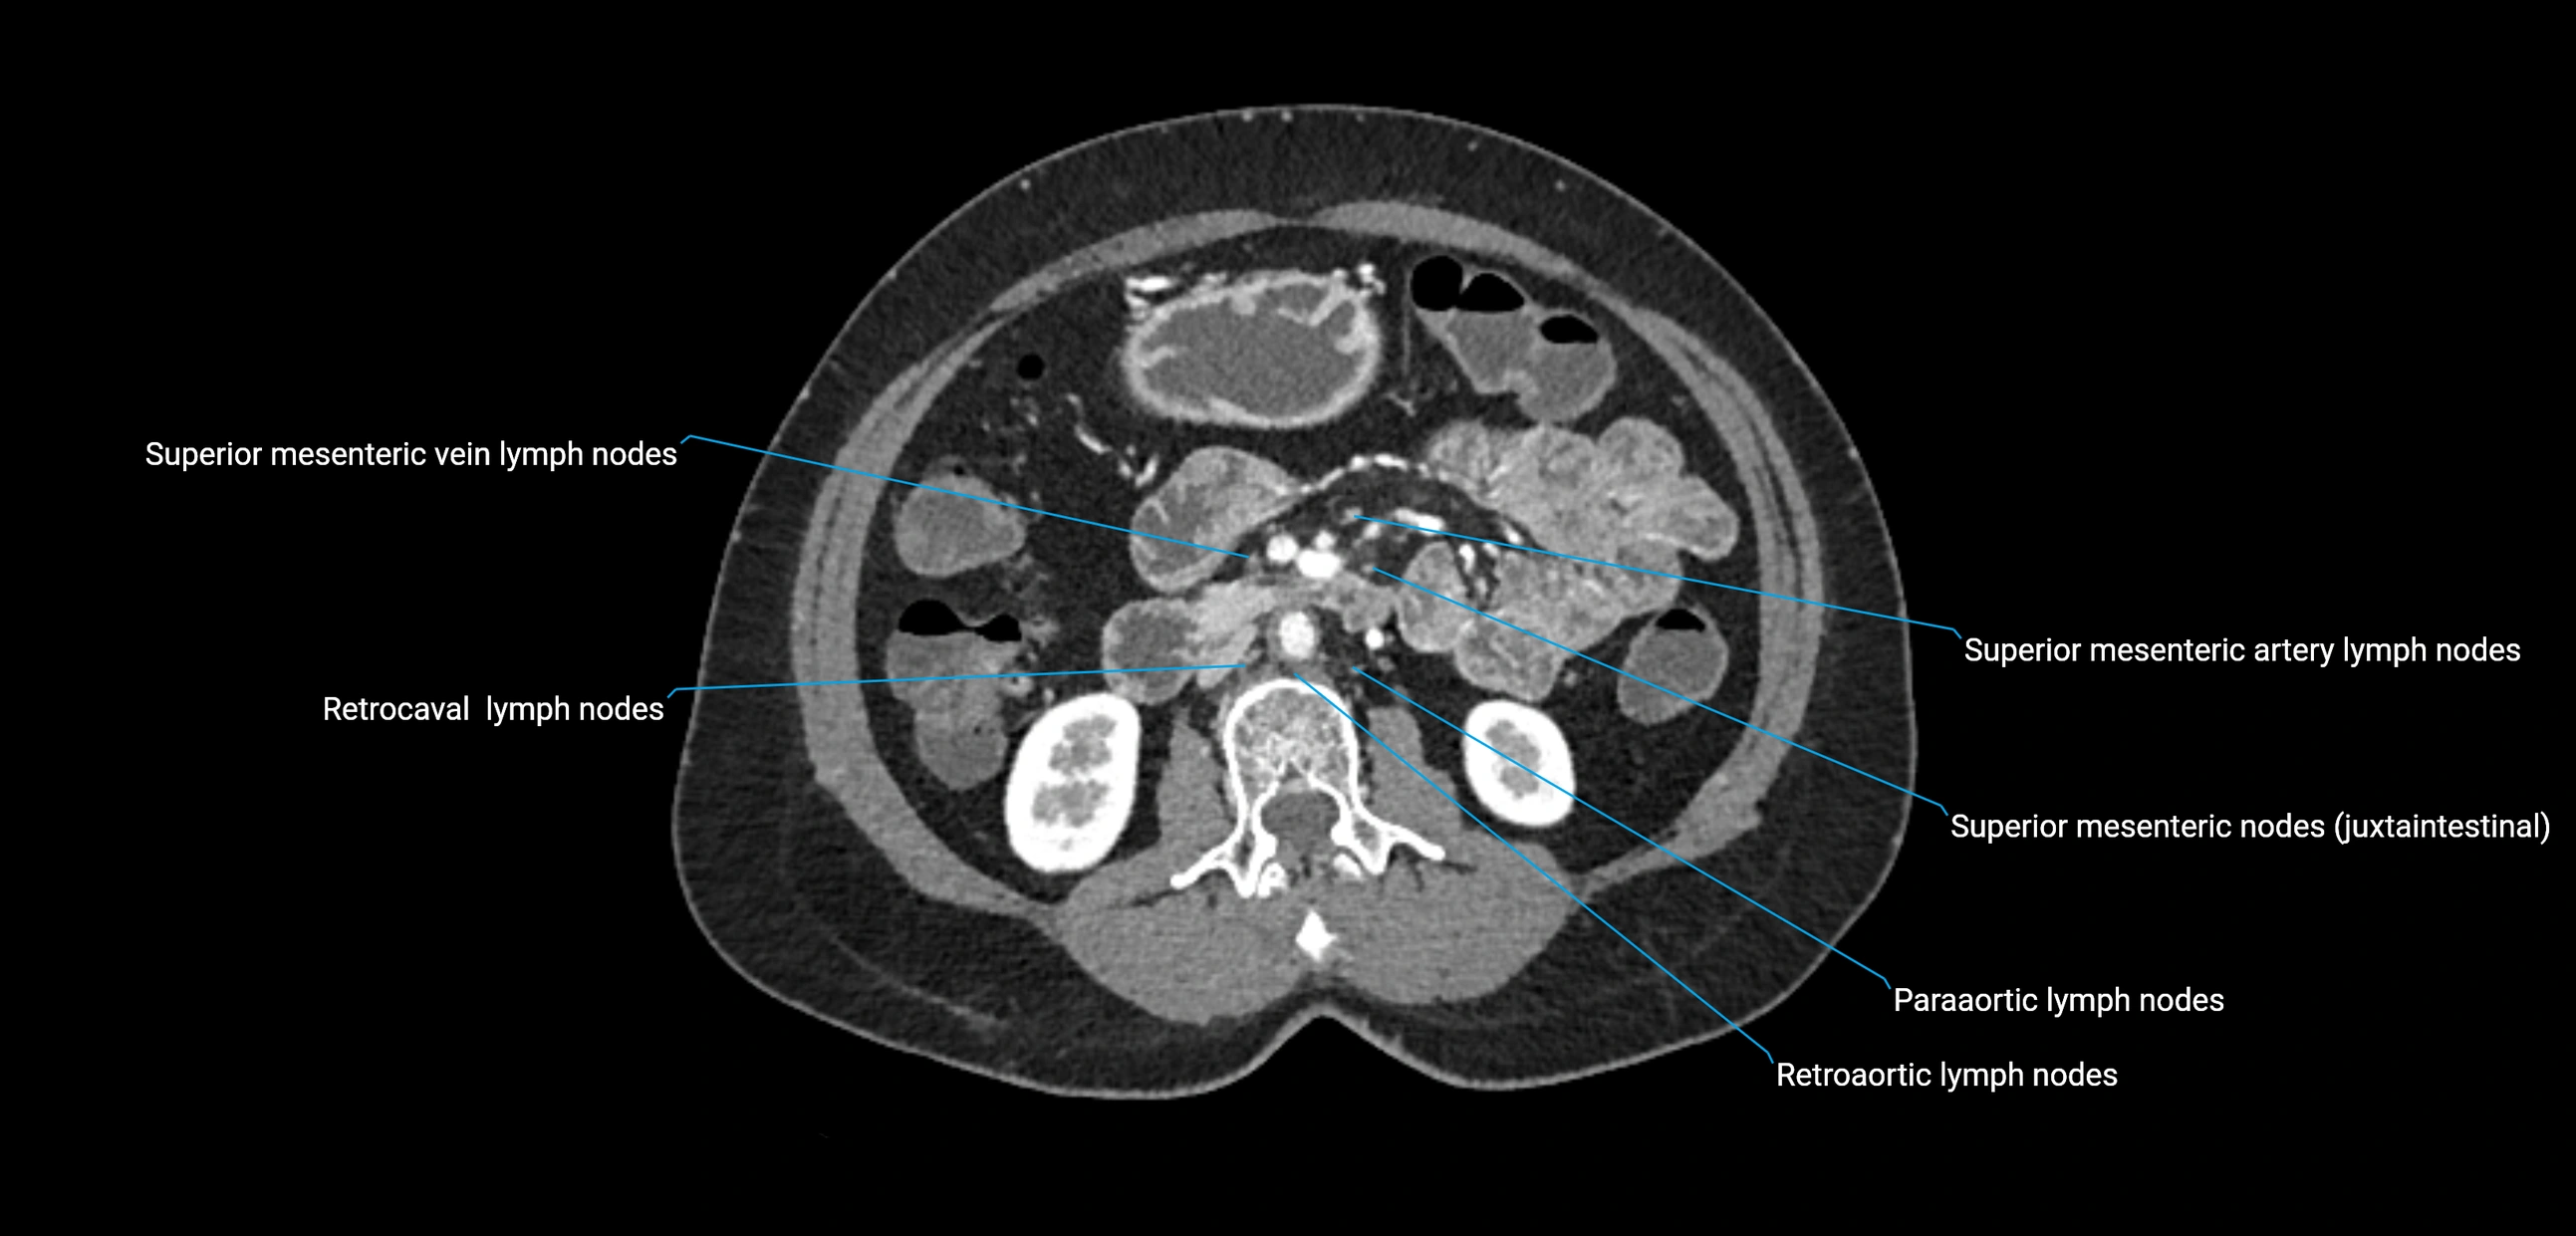

CT Appearance

CT Pre-Contrast:

• Nodes appear as soft-tissue density nodules adjacent to the aorta and IVC

• Calcification may be seen in chronic infections (e.g., tuberculosis)

CT Post-Contrast:

• Normal nodes enhance homogeneously

• Malignant nodes may show heterogeneous enhancement, central necrosis, or conglomerate formation

• Size >1 cm short axis is suspicious, though morphology and distribution are equally important

CT Venography (CTV):

• Demonstrates nodal encasement or compression of adjacent vessels (aorta, IVC, renal veins)

• Useful in staging testicular and ovarian malignancies

• Provides 3D reconstructions for retroperitoneal lymph node dissection planning